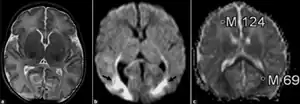

| Neonatal adrenoleukodystrophy a) The axial T2-weighted MR image is normal (b) the diffusion-weighted image (b = 1000 sec/mm2) reveals high-signal changes in the splenium of the corpus callosum, and occipital lobes (black arrows) c) the ADC map reveals that the ADC values of the involved regions is low (0.69 × 10–3 mm2/sec), compared to the frontal regions (1.24 × 10–3 mm2/s). | |